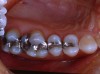

Figure 8 shows the preparations. It was determined that with this quadrant of teeth that No. 5 could be restored with a direct Class II composite (Premise). Tooth No. 4 was a little more involved and because the molars were going to have to be restored indirectly, it was decided to restore this tooth with an inlay. Teeth Nos. 2 and 3 had solid, strong, uninvolved buccal cusps. The functional lingual cusps that tested positive for fracture were the only cusps that required full-coverage protection. Therefore, an onlay design provided the protection required, yet allowed for a dramatic reduction in the amount of healthy tooth structure that needed to be removed.

Tooth No. 2 was restored with a gold onlay. However, the patient’s esthetic requirements dictated the use of tooth-colored material for the indirect restorations on teeth Nos. 3 and 4. Indirect composite has proven to be an excellent restorative material20,21 and was the material chosen for the final restorations. Figure 9 shows the final laboratory work with the gold onlay on tooth No. 2, and the indirect composite (belleGlass HP [now Premise Indirect], Kerr Corporation) inlay and onlay.

Figure 8  The inlay and onlay preparations.

Figure 8

Figure 9  The model work for the conservative restorations.

Figure 9